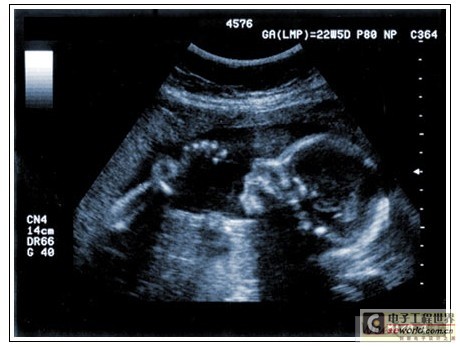

通過發(fā)射超聲能量進入人體,接收并處理返回的反射信號,相控陣超聲系統(tǒng)可以生成體內(nèi)器官和結(jié)構(gòu)的圖像,映射血液流動和組織運動,同時提供高準確度的血流速度信息。傳統(tǒng)設(shè)計中,構(gòu)建這樣的成像系統(tǒng)需要大量的高性能相控陣發(fā)射器和接收器,使得車載設(shè)備體積龐大且價格昂貴。近年來,隨著集成工藝的進步,設(shè)計人員能夠獲得小尺寸、低成本而且高度便攜的成像系統(tǒng)方案,并可達到接近大型成像設(shè)備的性能指標。而新的設(shè)計挑戰(zhàn)依然存在,即在進一步提高方案集成度的同時提高系統(tǒng)性能和診斷能力。